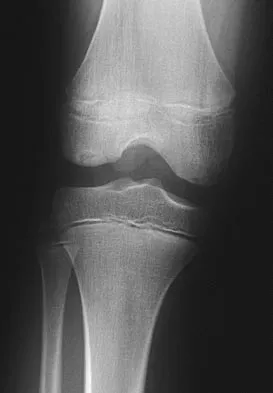

Question 59 High Yield

Figures 5a and 5b show the radiographs of an active 52-year-old man who has increasing knee pain and progressive varus deformity after undergoing total knee arthroplasty 7 years ago. Examination reveals a small effusion, but he has good motion and stability. What is the most likely diagnosis?

Detailed Explanation

The radiographs show narrowing of the medial joint space, which indicates polyethylene wear and progressive varus alignment. Wear particles incite osteolytic lesions like the one seen on the lateral radiograph. O'Rourke MR, Callaghan JJ, Goetz DG, et al: Osteolysis associated with a cemented modular posterior-cruciate-substituting total knee design. J Bone Joint Surg Am 2002;84:1362-1371.